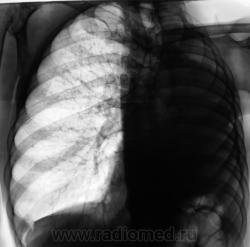

Пациент, заслуженный в прошлом, подданный "Его Величества", 10 лет тому был прооперирован - левосторонняя пульмонэктомия по поводу фиброзно-кавернозного туберкулёза. Вроде-бы все было нормально, время - от времени шел на встречу к работникам фтизиатрической службы, являясь после неоднократных напоминаний, делая им одолжение... Но в последние 3 года пропал. 2 месяца тому был найден, приглашен и явился. Чувствовал себя хорошо, даже не стал возражать против рентгенографии. Но смутили очаги, которых ранее не было в верхней доле правого лёгкого.

Повторили и "прямую", и произвели томограммы.

Очаговый туберкулез верхней доли?

Tbc, ещё может и в нижней есть засев

туберкулёз правого лёгкого.

А, не большая-ли площадь для очагового?

.....При гематогенном генезе подострого диссеминированого туберкулеза однотипная очаговая диссеминация локализуется в верхних и кортикальных отделах легких....

Вот-вот - диссеменация..

Очаги крупноваты для диссеминированного Tbc.

Так не миллиарный же, а просто - дисеминированый...если так посмотреть на вопрос?

Мы тоже склонились в пользу диссеминированного.

Важно то, что мы "посылальщика" упаковали. Выставлен диссеминированный туберкулёз.